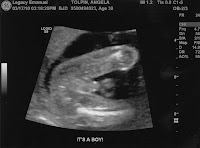

Ultrasound Results